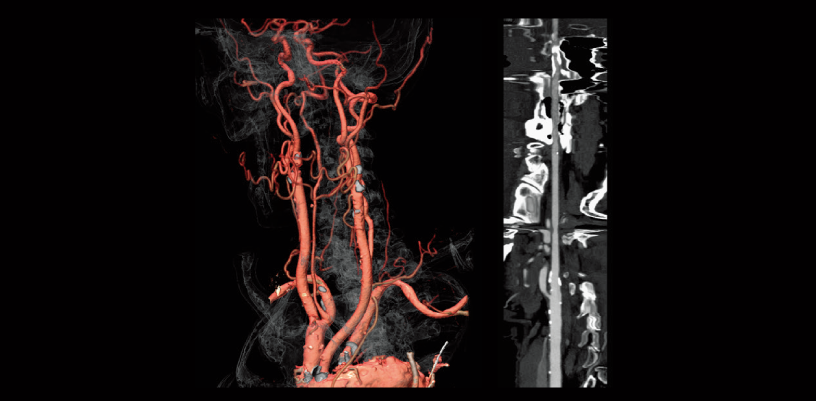

FBP(izquierda)

Intelli IPV(derecha)

Estenosis de la arteria carótida común